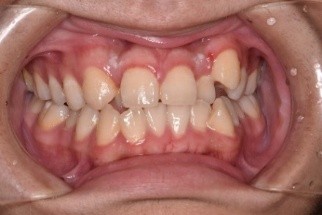

(↑矯正治療前)

こちらの患者様は前歯の歯並び改善を目的に来院されました。患者様の歯をきれいに並べるには歯列のスペースが足りなかったため抜歯を行い、その後ワイヤー矯正から行っていきました。